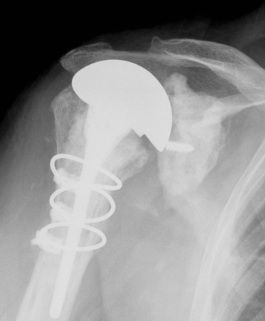

Shoulder Hemiarthroplasty Rotator Cuff FailureTSR Superior EscapeaTSA failed cuffTSR Failed Rotator CUff

Overstuffed aTSARevision to revTSA